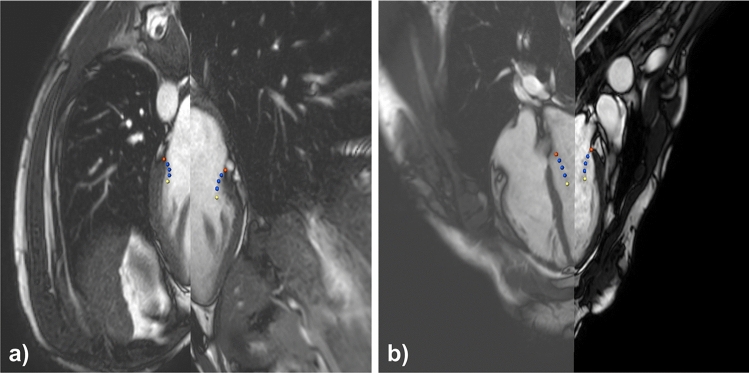

Mitral valve annotation

Three domain experts segmented the mitral valve in the simulated images using a dedicated prototypical software solution as shown in Fig. 4 (average segmentation time approximately 20 min per case; SAX 3.5 min, rLAX6 3.5 min, rLAX9 5 min and rLAX18 8 min); the valve annulus is highlighted with red points and the orange contour. The yellow points represent the valve orifice. The users annotated two points for the annulus, two for the leaflet ends (defining the orifice) and a variable number of points for leaflet contours on each rotational plane (rLAX). In the SAX stack the valve annotation was performed using spline contours.

Fig. 4.

Annotation tools. Annotation software interface for the interactive annotation of the radial long axis (rLAX) images (a) and short axis (SAX) image data (b). Red points indicate the annulus, blue ones the leaflets and the yellow ones the leaflets end (orifice)